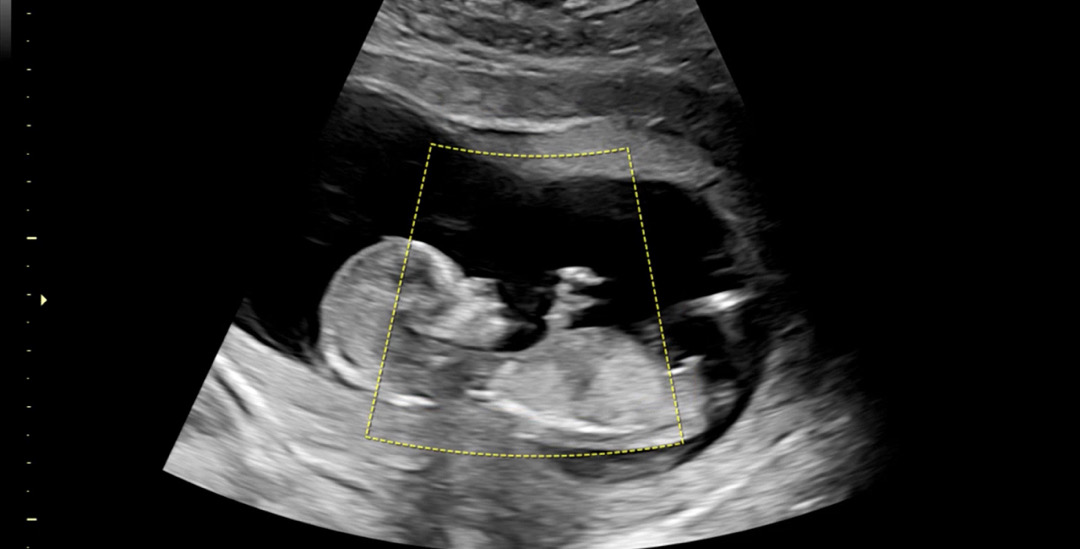

오늘 1차 기형아검사하면서 초음파보고왔어요~~ 각도법 고수님들 성별 예측해주세요!